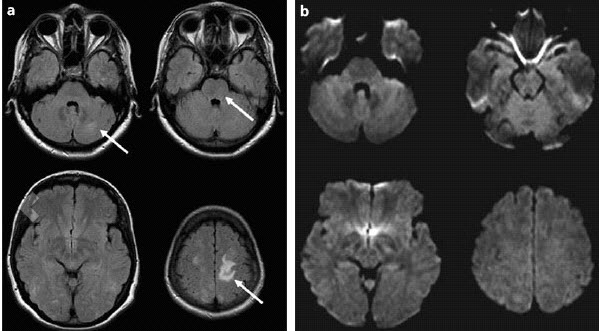

• CT and MRI show diffuse cerebral edema.